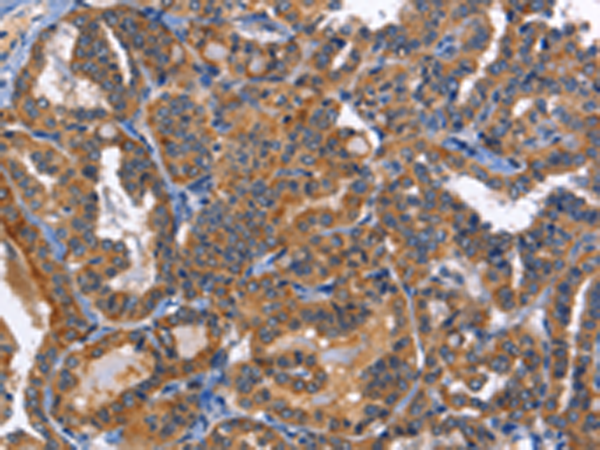

分类: 科研抗体货号: P07952别名: BARK2; ADRBK2应用: IHC反应种属: Human, Rat